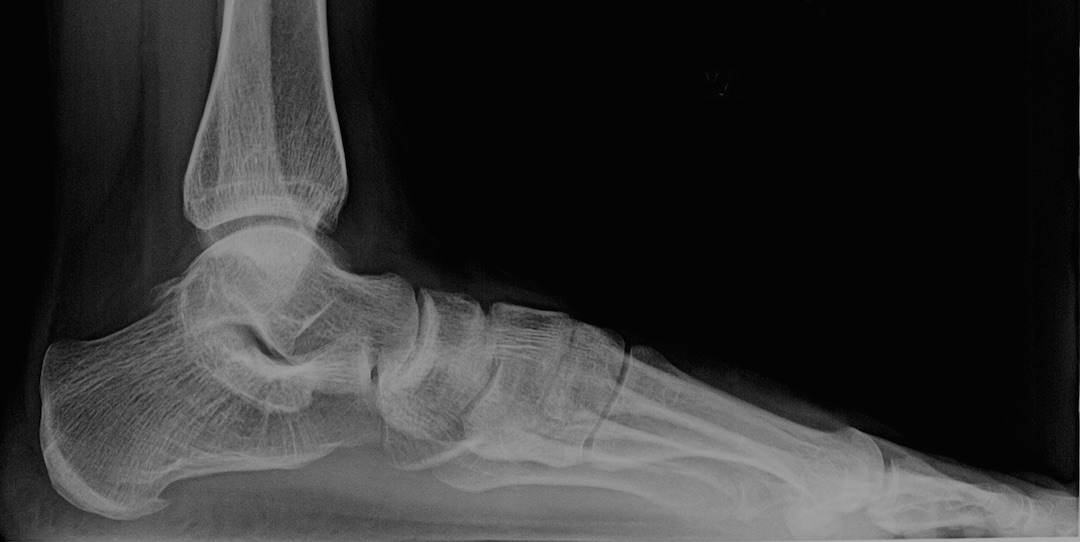

The x-ray above shows several things. First, my bones are very thin. The white parts should be much whiter for someone my age. The osteoporosis is throughout my ankle and heel, at the base of my tibia and fibula, and on the ends of the metatarsal bones. The remineralization is visible as the “spiderweb” or white crosshatching lines at the ends of my bones. The solid white lines are where the minerals (calcium, magnesium, etc.) are redepositing.

The doctor talked fast and wasn’t really ready to listen to my program for rebuilding my bones. It is a little more than walking and taking 4 pills, even though those are the basis of my progress. When I was really sick, I thought it was more worthwhile to take 20 minutes to walk a short distance (from my door to the car waiting for me outside) than to use a wheel chair and do it in three minutes. As I reduced the nervous system infection load and my overall toxicity level, I could do more, so I did. I walked whenever I could. I did yoga whenever I could. I stood whenever I could. It clearly wasn’t enough, given how thin my bones still are, but I did everything I could manage to use my body.